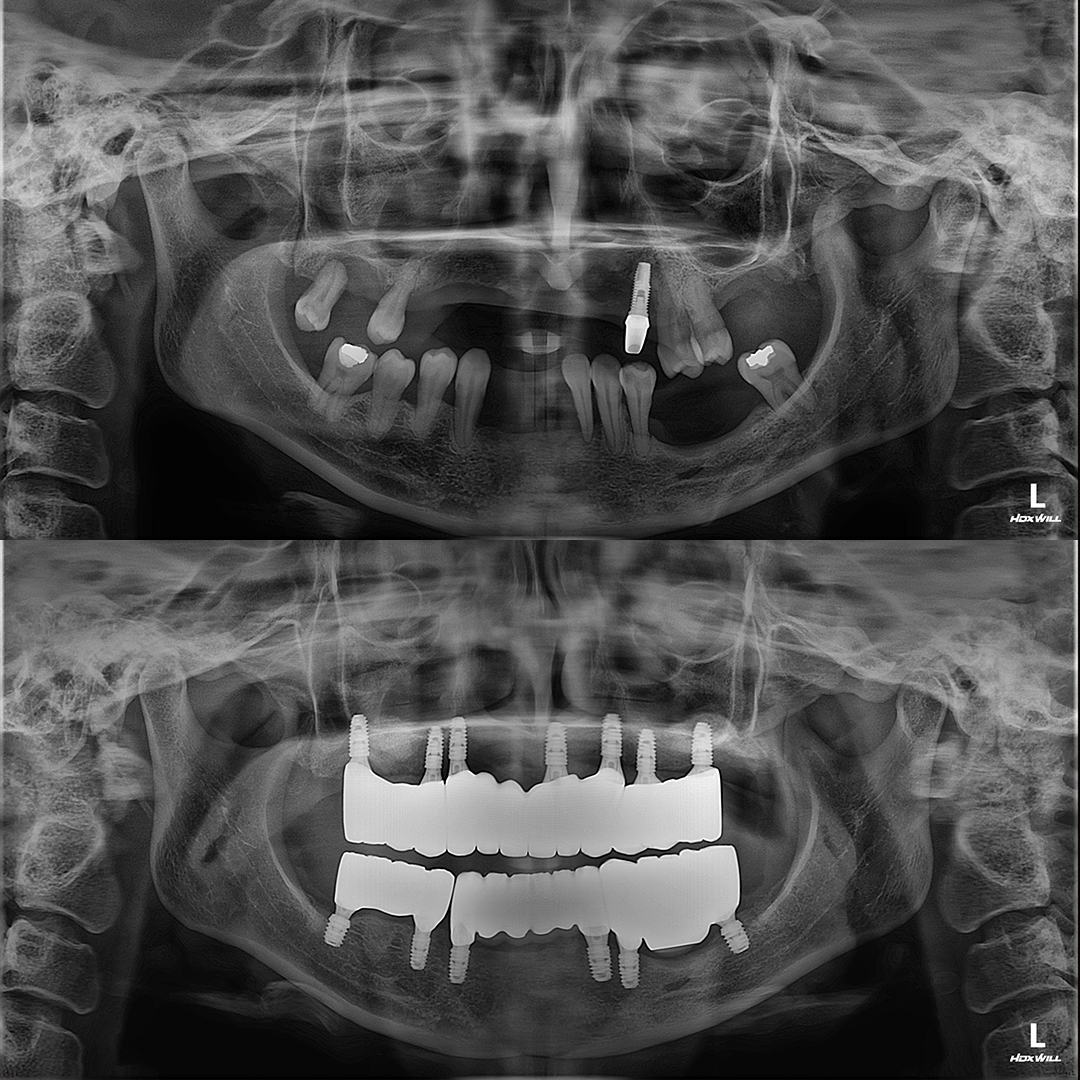

평균 악당 30분의 빠른 식립시간, 치료 케이스 다수 보유

전체 임플란트

상·하악 전체 치아를 대체하는 임플란트로 최소한의 식립을 통해

자연치아와 비슷한 기능을 수행할 수 있도록 합니다.